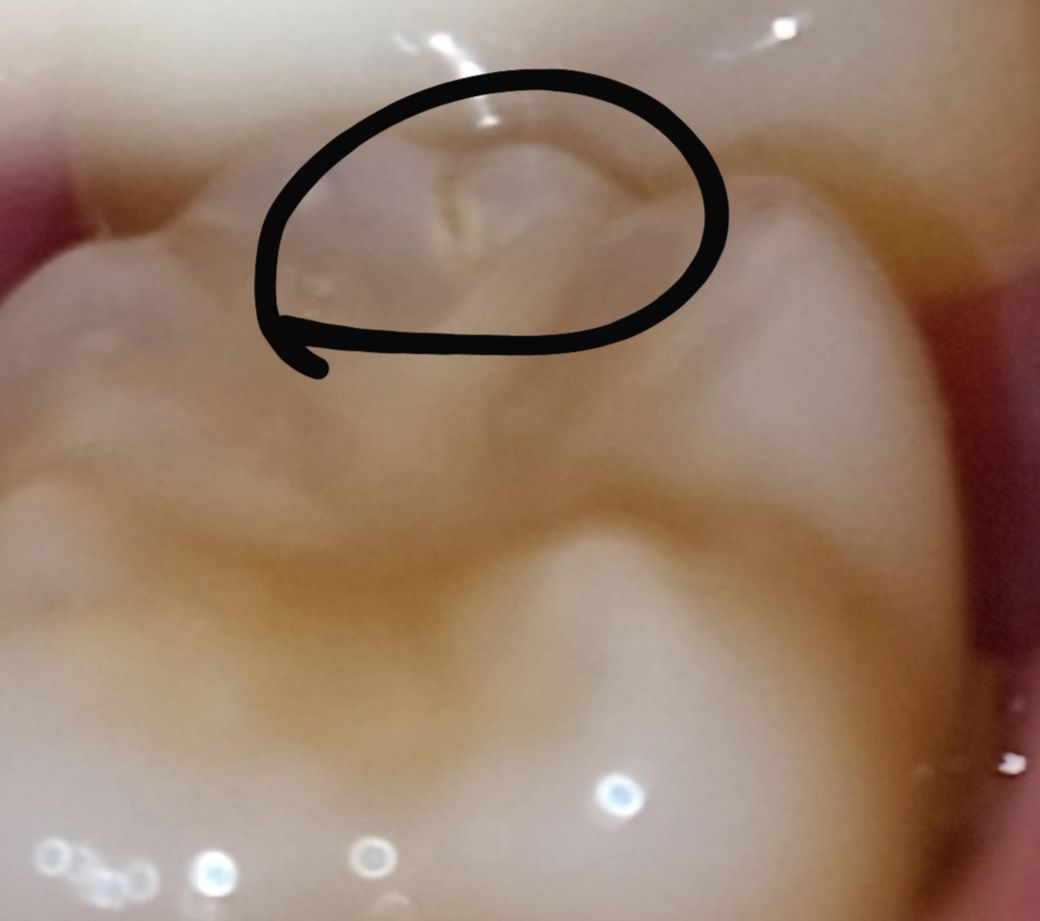

치아 파절됐는지와 치료법이 궁금합니다

두 어금니에 저렇게 검은색으로 금이 간 것 같은데 이게 뿌리염증과 발치로 이어질 수 있나요? 아직 학생이라 너무 걱정스럽습니다.

간단한 치료로 금간걸 매꿀 수 있는 지 궁금합니다.

한쪽 어금니에서 지속적으로 질긴걸 씹을때 시린 느낌이 간헐적으로 있는데, 최근 치과 검진과

엑스레이에서는 아무 문제 없다고 하셨는데 다시 가봐야할까요?

선상으로 충치가 생긴 것으로 보입니다. 치과에 가서 충치 치료하면 될 것으로 보입니다. 만약 밑으로 많이 진행되어 씹을 때 시린 느낌 온다면 신경치료 까지 생각해야 합니다.

2. 정확한 이유는 알기 어려우나 치아 법랑질 표면에 균열이 발생하여 금이간 것으로 보이는데 내부까지 심하게 금이 간 게 아니라면 균열부위를 제거하고 레진으로 떼워주면 될 것 같습니다.